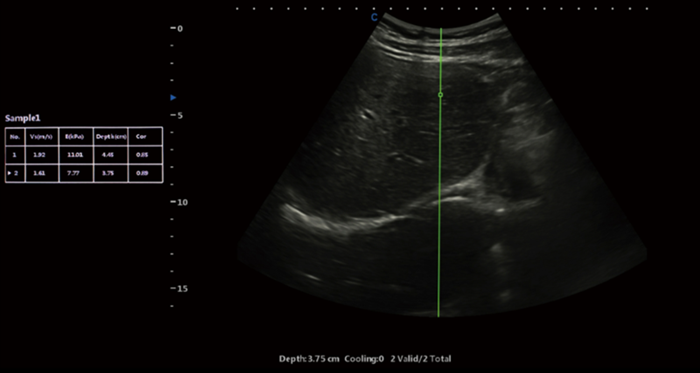

Shear wave elastography is a non-invasive imaging technique that measures tissue stiffness by generating and analyzing shear waves within the body. By utilizing ultrasound technology, shear wave elastography offers a unique perspective into the mechanical properties of tissues, enabling healthcare professionals to diagnose a wide range of conditions accurately.

Shear wave elastography relies on the propagation of shear waves through tissues. These waves are generated by the application of acoustic radiation force, which causes displacements within the tissue. By measuring the speed at which these waves travel, shear wave elastography can determine the elasticity and stiffness of tissues. This information is then visualized using color maps, providing clinicians with valuable diagnostic information.

Shear wave elastography represents a significant advancement in the field of diagnostic imaging. With its ability to assess tissue stiffness non-invasively and provide valuable diagnostic information, this technique has revolutionized medical imaging across various specialties. From liver disease assessment to breast lesion characterization and musculoskeletal evaluations, shear wave elastography continues to enhance our understanding and management of numerous conditions. XBit 90 has both P-SWE point shear wave imaging and 2D-SWE surface shear wave imaging. Provide a variety of quantitative analysis parameters, such as velocity values, Young's modulus, and so on. Embracing this cutting-edge technology can empower healthcare professionals to deliver superior patient care and make more informed clinical decisions.